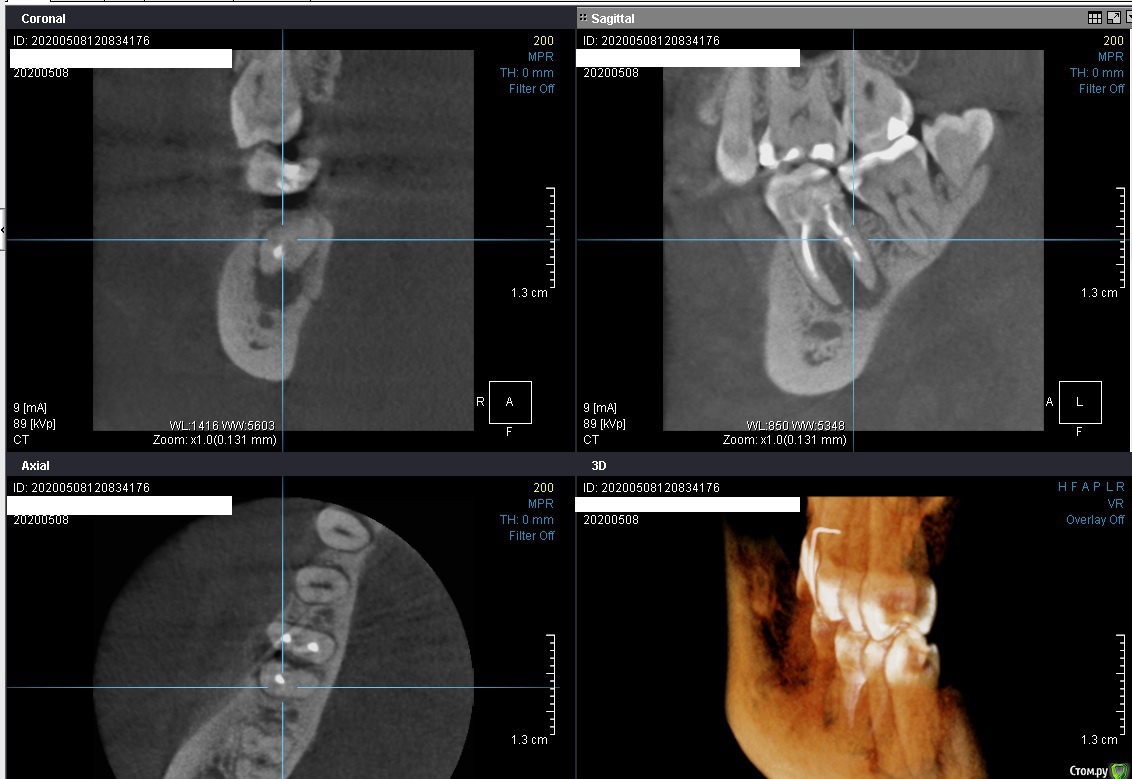

Ксения Д Опубликовано 8 мая, 2020 Поделиться Опубликовано 8 мая, 2020 Добрый день! Подскажите, есть ли возможность сохранить зуб?На данный момент на десне образовался свищевой ход.Доктор говорит, что раз воспаление между корнями зуба, то тут только удалять. Спасибо. Ссылка на комментарий